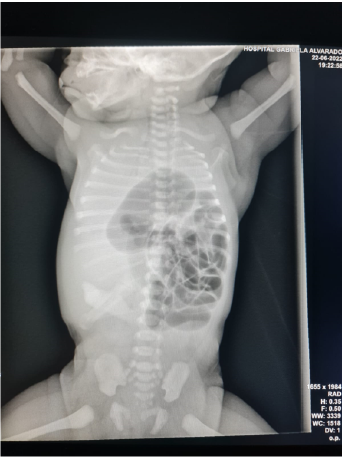

Left Bochdalek Diaphragmatic Hernia in Newborn at Hospital Gabriela Alvarado, Honduras, 2022

Scarlett Nabila Rodríguez Flores, Osvaldo José Munguía Velásquez, David Nicolás Mendoza Irías, Josué David Molina Paz, Jennifer Lizeth Quintero Lira, Ibeth Georgina Cedillo Velásquez and Oscar Fawed Ortega Reyes. 5(10): 66-68.